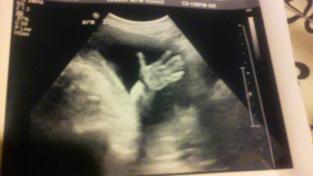

Pequeña, callada parece que no es la importante de la conversación. Esta de 12 semanas de embarazo. Viene a la asociación acompañada de las únicas personas que no la «aconsejan» abortar. En el instituto la trabajadora social le ha aconsejado abortar, sus amigas, su madre la ha amenazado con pasarle la tutela a la comunidad de Madrid. La madre la está presionando dejándola sin comer, sin medicamentos, cada día la madre va al instituto para buscar aliados para obligar a su hija a abortar. Y los encuentra. Pero una trabajadora de allí se enfrenta a todos. Tiene buena fama con el alumnado, la escucha, la apoya y la protege. Y ella por fin encuentra un asidero.